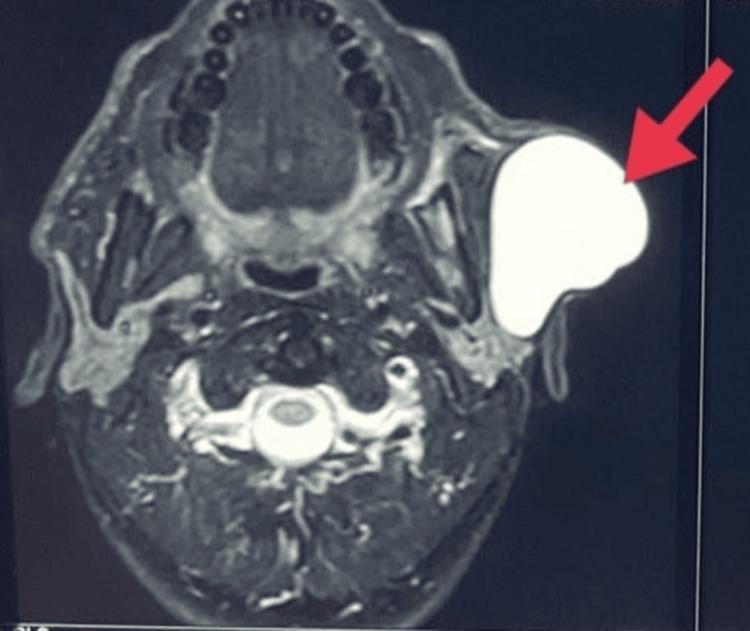

Epidermoid Cyst Mimicking a Cystic Parotid Tumor: A Diagnostic Dilemma Deciphered Intraoperatively.

Cystic lesions in the preauricular may have various histological origins, ranging from the skin to the acinar and non-acinar lesions from the parotid. Though advanced radiological investigations provide a good insight into the diagnosis of these lesions, diagnostic dilemmas may still prevail and warrant good clinical and surgical acumen to provide optimal treatment. The aim of the current report is to describe a case of an epidermoid cyst that mimicked a parotid cyst and discuss in detail the probable differential diagnosis and their management strategies.

耳前囊性病变可能有多种组织学起源,范围从皮肤到腮腺的腺泡性和非腺泡性病变。尽管先进的影像学检查能很好地洞察这些病变的诊断,但诊断难题可能仍然存在,需要良好的临床和手术敏锐度来提供最佳治疗。本报告的目的是描述一例酷似腮腺囊肿的表皮样囊肿病例,并详细讨论可能的鉴别诊断及其管理策略。